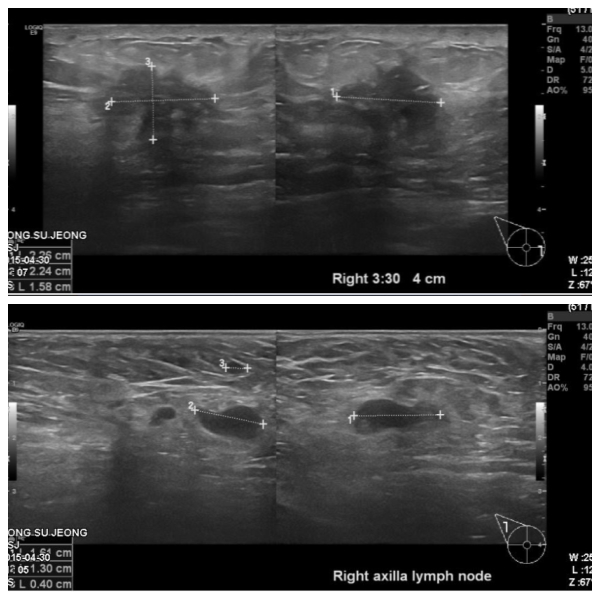

건강검진상 이상 소견으로 내원하신 50대 여성 분으로  우측 침윤성 유관암 진단

되었으며, 겨드랑이 전이로 확인 되었습니다.